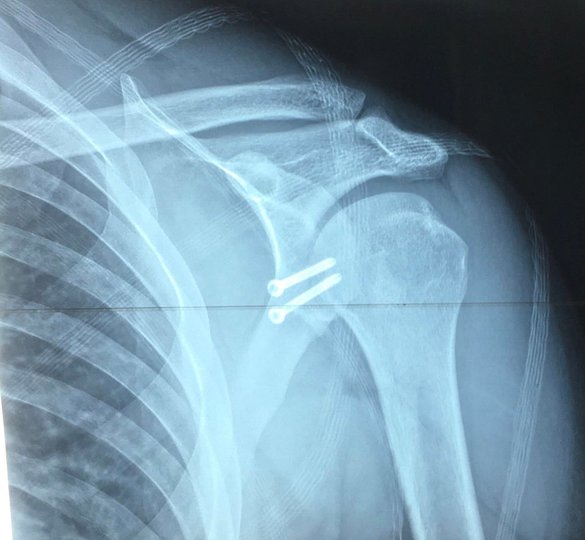

Якщо хочете читати головні новини дня оперативно Додайте ZAXID.NET у вибрані в GoogleХірурги вирішили провести йому операцію по стабілізації плечового суглоба за методом Латерже. «Хірурги відділення артроскопії та малоінвазивних отропедичних втручань Волинської обласної клінічної лікарні вперше провели операцію по стабілізації плечового суглоба з приводу звичного вивиху плеча (операцію Латерже). Таке оперативне втручання має свої труднощі, оскільки є високий ризик пошкодити нервові та судинні структури кінцівки. Саме тому за такі втручання беруться не всі та й не скрізь», – йдеться у повідомленні прес-служби медзакладу.

Відомо, що операція минула успішно, травмований вже може рухати рукою. Наразі пацієнт проходить реабілітацію.